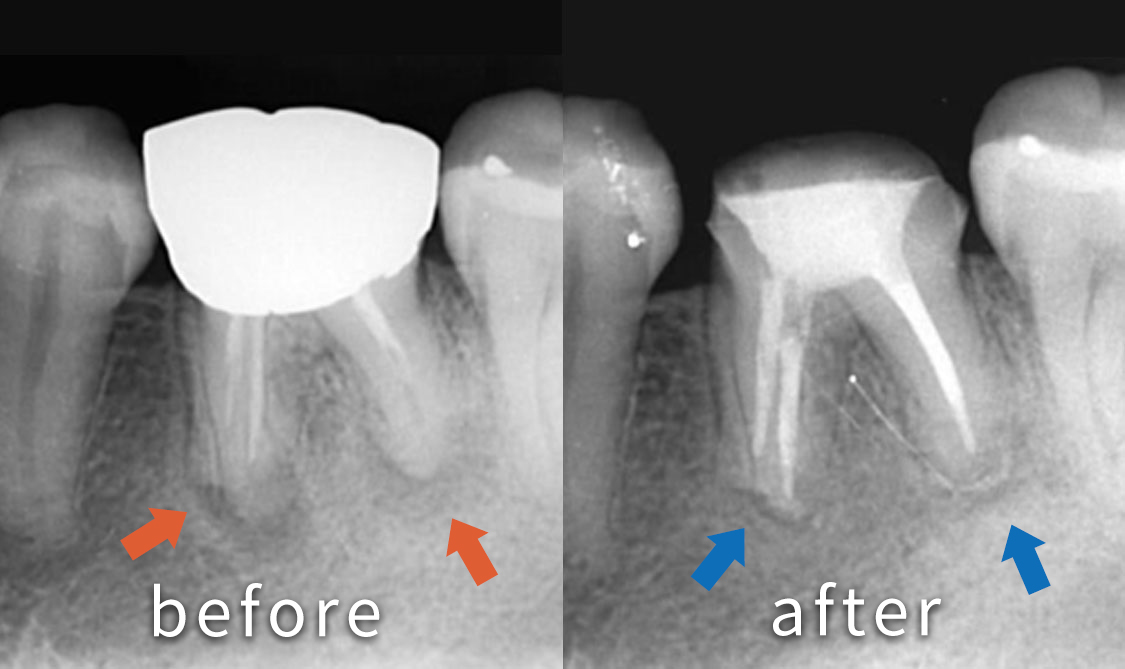

症例

慢性根尖性歯周組織炎

経緯及び経過

奥歯が痛くて噛めないといった悩みで来院された患者さんです。 レントゲンを撮影すると奥歯の根の先が膿んでいる状態でした。

根の中の古いお薬を取り除き、根の中を綺麗にした状態で新しいお薬を詰めています。根の先の病気(矢印の部分)の影が小さくなり、経過良好です。